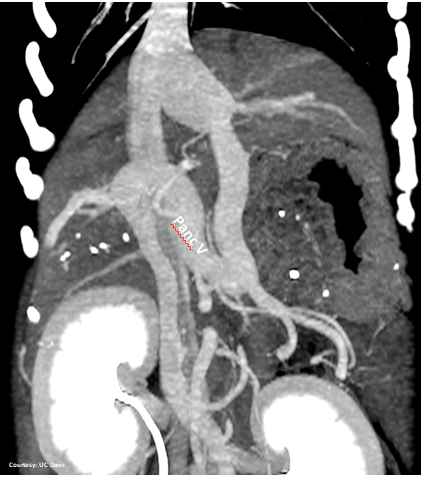

INTRAHEPATIC ENTRANCE

WEISSE 2022